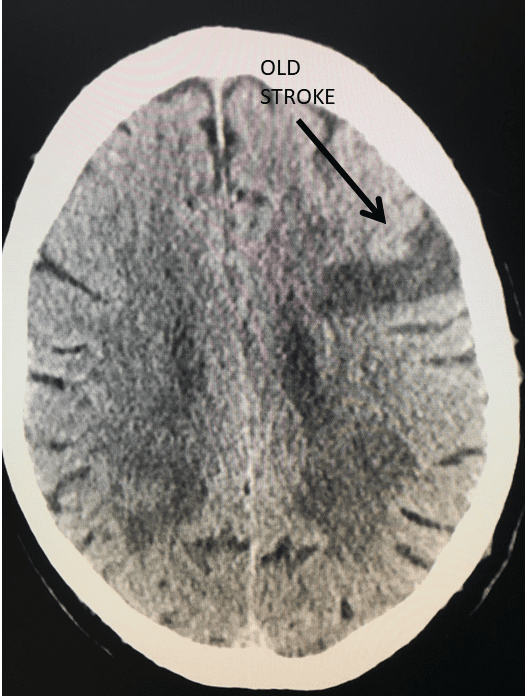

Figure 1.

This 77-year-old man with a history of stroke in 2013 presented to a small community hospital with aphasia upon awakening. Given the unclear timing of onset of his symptoms he was not deemed a candidate for intravenous thrombolytic. His NIHSS was 2 in the emergency room. He was admitted to the hospital where a CT (Figure 1) and CTA were performed showing a left frontal small infarct and severe extracranial carotid stenosis on the left. MRI could not be performed because of the patient’s pacemaker. Examination was significant for an awake gentleman with normal cranial nerve function and normal motor exam but significant expressive aphasia. Receptive aphasia was intact. He was placed on Aspirin.